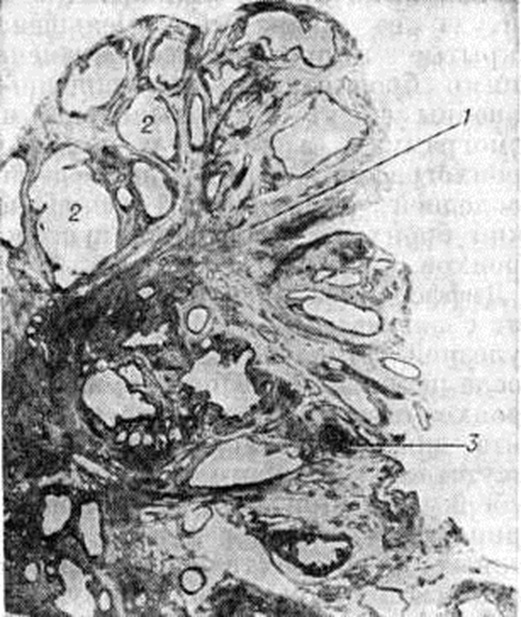

Первичный аффект (смотри полный свод знаний: Аффект первичный) формируется чаще во 2—5-м сегментах лёгких под плеврой в виде очага казеозного бронхиолита или альвеолита. Вокруг очага казеозного некроза имеется слой специфической грануляционной ткани, состоящей из эпителиоидных, лимфоидных и гигантских клеток Пирогова—Лангханса (смотри полный свод знаний: Гигантские клетки). Первичный аффект обычно окружён широкой зоной перифокального воспаления (серозного или серозно-фибринозного). В лимфатических сосудах, по которым осуществляется отток лимфы от первичного аффекта к корню лёгкого, обнаруживаются воспалительные изменения — туберкулёзный лимфангиит. Регионарные лимфатических, узлы корня лёгкого увеличены, уплотнены. Некоторые из них полностью замещены массами казеозного некроза, другие содержат лишь отдельные очаги некроза и туберкулёзные гранулемы (рисунок 1). При прогрессировании процесса изменения наблюдаются как в первичном очаге, так и в регионарных лимфатических, узлах. Первичный очаг при этом увеличивается в размерах, в нем нарастают экссудативные казеозно-некротические изменения; казеозному некрозу подвергается и зона перифокального воспаления. В грануляционной ткани появляется большое количество сегментоядерных лейкоцитов. При вовлечении в процесс бронхов в их стенках развивается воспаление по типу казеозного эндо-, мезо и панбронхита, наблюдаются казеозный бронхиолит и казеозная бронхолобулярная пневмония. При расплавлении в первичном очаге масс казеозного некроза может наступить их прорыв в просвет прилежащих бронхов с образованием острой каверны (смотри полный свод знаний). Распространение туберкулёзного процесса по бронхам ведёт к острой бронхогенной диссеминации с формированием ацинозных или ацинозно-лобулярных очагов казеозной пневмонии. В настоящий, время такие остро прогрессирующие формы первичного Туберкулёз органов дыхания встречаются редко. Чаще наблюдается ограничение первичного очага и рассасывание перифокального воспаления. Затем по периферии первичного очага образуется фиброзная капсула. Позднее массы казеозного некроза подвергаются уплотнению с отложением в них солей кальция (смотри полный свод знаний: Петрификат). Такой инкапсулированный обызвествлённый очаг называется очагом Гона. Воспаление в лимфатических, сосудах стихает, в них развиваются фиброзные изменения. Аналогичные процессы наблюдаются в очагах бронхогенной или гематогенной диссеминации, если они имели место.

Рис. 1.

Гистотопограмма лёгкого при первичном туберкулёзном комплексе: 1 — очаг казеозного некроза в лёгочной ткани в стадии начавшегося отграничения; 2 — казеозный некроз лимфатических узлов в области корня лёгкого; 3 — воспалительные изменения лимфатических сосудов, соединяющих очаг в лёгком с лимфатическими узлами корня лёгкого — туберкулёзный лимфангиит.